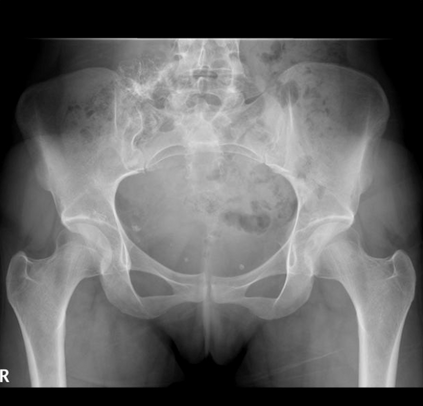

In this study, we aim to initiate the development of Radiology Foundation Model, termed as RadFM.We consider the construction of foundational models from the perspectives of data, model design, and evaluation thoroughly. Our contribution can be concluded as follows: (i), we construct a large-scale Medical Multi-modal Dataset, MedMD, consisting of 16M 2D and 3D medical scans. To the best of our knowledge, this is the first multi-modal dataset containing 3D medical scans. (ii), We propose an architecture that enables visually conditioned generative pre-training, allowing for the integration of text input interleaved with 2D or 3D medical scans to generate response for diverse radiologic tasks. The model was initially pre-trained on MedMD and subsequently domain-specific fine-tuned on RadMD, a radiologic cleaned version of MedMD, containing 3M radiologic visual-language pairs. (iii), we propose a new evaluation benchmark that comprises five tasks, aiming to comprehensively assess the capability of foundation models in handling practical clinical problems. Our experimental results confirm that RadFM significantly outperforms existing multi-modal foundation models. The codes, data, and model checkpoint will all be made publicly available to promote further research and development in the field.